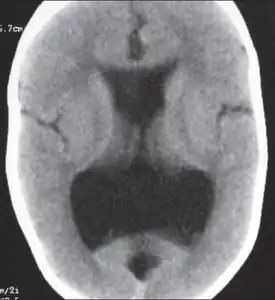

Image indicates colpocephaly with septal agenesis

Colpocephaly is characterized by disproportionately large occipital horns of the lateral ventricles (also frontal and temporal ventricles in some cases). MRI and CT scans of patients demonstrate abnormally thick gray matter with thin poorly myelinated white matter. This happens as a result of partial or complete absence of the corpus callosum. Corpus callosum is the band of white matter connecting the two cerebral hemispheres. The corpus callosum plays an extremely important role in interhemispheric communication, thus lack of or absence of these neural fibers results in a number of disabilities.[12]

The lemon sign on CT scans of patients refers to the shape of the fetal skull when the frontal bones lose their normal convex contour and appear flattened or inwardly scalloped. This gives the skull a shape similar to that of a lemon. The sign is seen on transverse sonograms of the fetal cranium obtained at the level of the ventricles. A special case is found in literature where lissencephaly, colpocephaly, and septal agenesis are all present together. The CT scans of the patient shows the ventricular system having a unique appearance of a crown of a king. This is referred to as the 'CROWN SIGN'.[8]